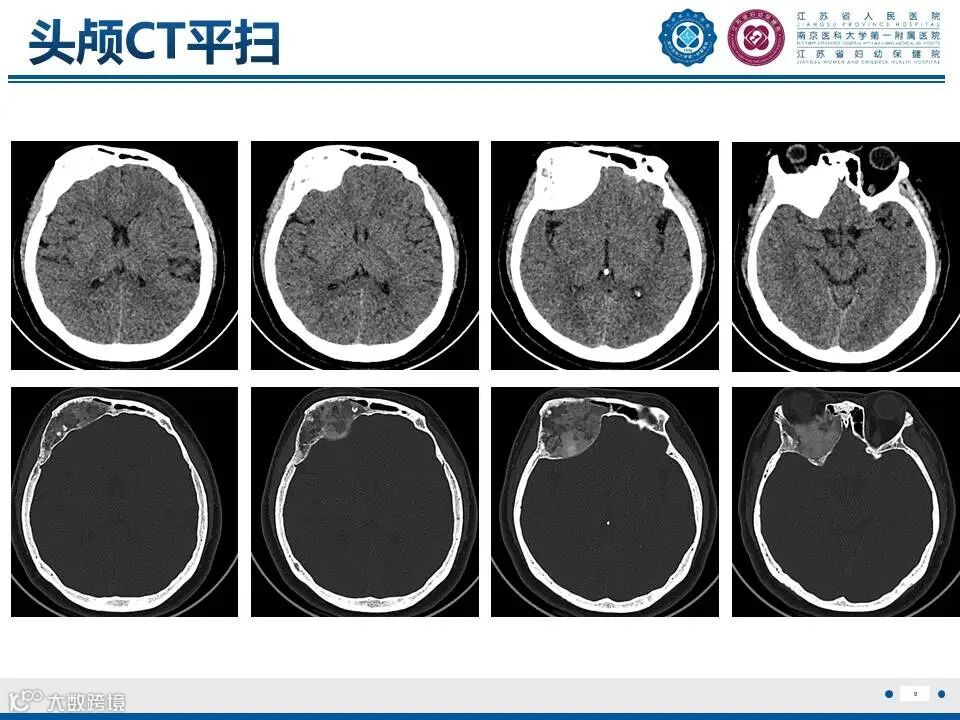

颅骨骨纤维异常增殖症——颅骨上的编织骨

颅骨骨纤维异常增殖症——颅骨上的编织骨 鼎湖影像